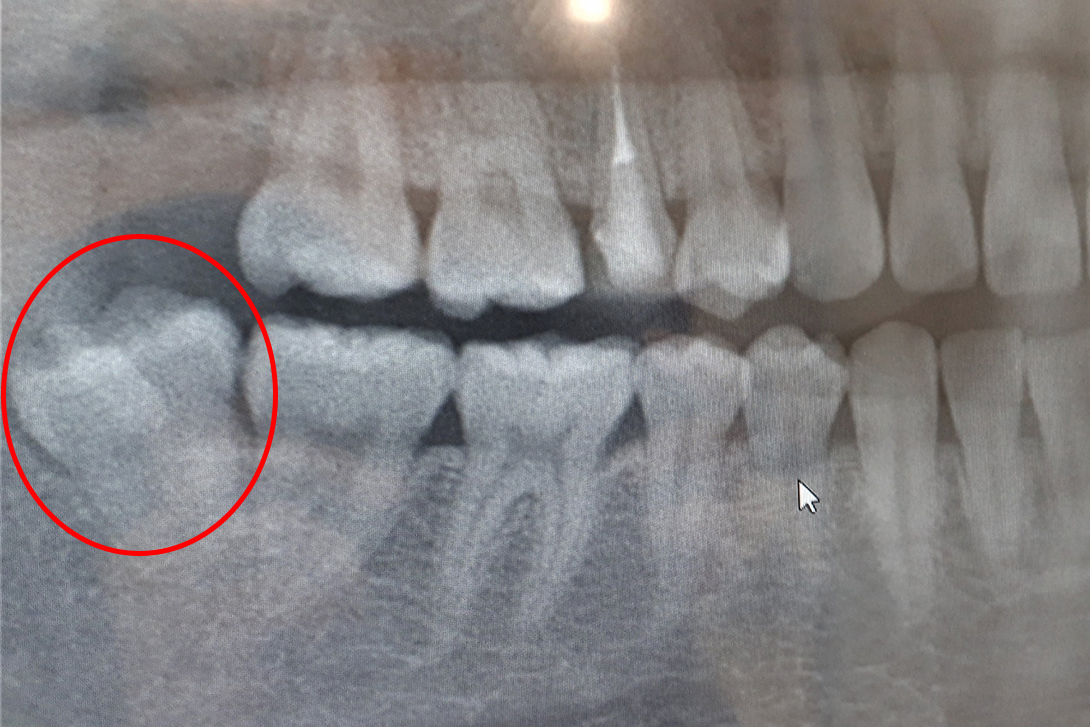

しかし、親知らずは他の歯よりもかなり遅く生えてくるため、歯の生えるスペースが不足している場合が多く、そのため斜めや横向きに生えたり、歯ぐきに埋没したまま生えてこなかったりとトラブルを引き起こしやすいのが特徴です。

親知らず自体がむし歯・歯周病になっている、親知らずの周囲の歯茎が腫れ・痛みを繰り返す、隣の歯を圧迫して悪影響を及ぼしているなど、問題がある場合は抜歯をおすすめします。

智歯(親知らず)や、埋伏歯(顎骨や歯肉に埋まっている状態の歯)等の難抜歯